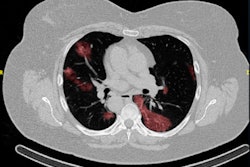

The best AI platforms have a wide range of labeling and segmentation options so that images can be presented correctly. With the RVAI platform from Robovision, the margins of the opacities in the lung are automatically identified by the "adaptive" brush tool. The lesions or abnormalities are simultaneously segmented in three different planes. In this figure, not all visible opacities have been segmented yet. Images courtesy of Dr. Erik Ranschaert, PhD.The added difficulty of COVID-19 lung abnormalities is they can be subtle and difficult to differentiate from other conditions. Last week, for example, Ranschaert and his colleagues at the Elisabeth-TweeSteden Hospital in Tilburg, the Netherlands, treated a patient with a pneumocystis carinii pneumonia infection. As in COVID-19 cases, this infection can give similar opacification on both sides of the lungs, so it requires great care and can be misdiagnosed, he pointed out.